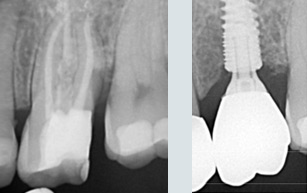

Une situation de pertes dentaires multiples et infections sous des racines naturelles.

Final : traitements de racines effectués et dents manquantes remplacées.